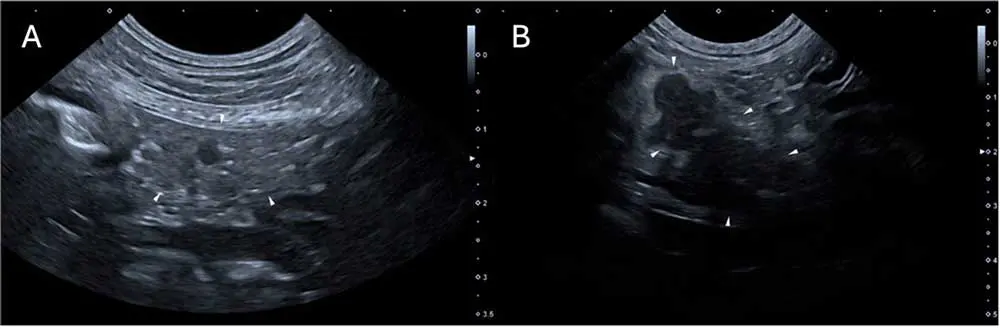

The bottom line is that AUS does not allow for the 100% confirmation or exclusion of CAP. Studies have suggested sensitivity of 70% to 88% for ultrasonographic changes, sometimes dependent on the criteria used21,40,42,43,49. Suggested criteria are identification of at least two highly suggestive changes: pancreatomegaly, pancreatic hypoechogenicity, pancreatic heterogenous echogenicity, hyperechoic mesentery (potentially the most commonly reported at 82% to 83%) and peripancreatic free fluid16,20,36,49,50. Potentially suggestive, but less important, signs are corrugated adjacent duodenum/colon, pancreatic cysts/abscesses, venous thrombosis, biliary/pancreatic duct dilation, thickening of the gastric/duodenal wall and signs of ileus36. Strong evidence exists that AUS findings change over time and may lag behind disease progression, as cPLI activity appears to increase first36,39. In two studies, at time of admission 12 out of 38 (32%) and 24 out of 37 (65%) dogs had at least two highly suggestive signs of CAP, but a further 12 out of 38 and 10 out of 37 (who mostly had no changes at all on admission) developed these after two to three days, for a total sensitivity of 68% to 92%36,39. Therefore, for dogs where CAP diagnosis is not clear but still suspected, repeating AUS after two to three days may be of significant aid (Figure 2).

As well as pancreatic changes, CAP can also be associated with changes to the local GI tract. Forty-seven % of dogs with CAP have GI wall changes, most commonly to the duodenum (71%; Figure 3)16.